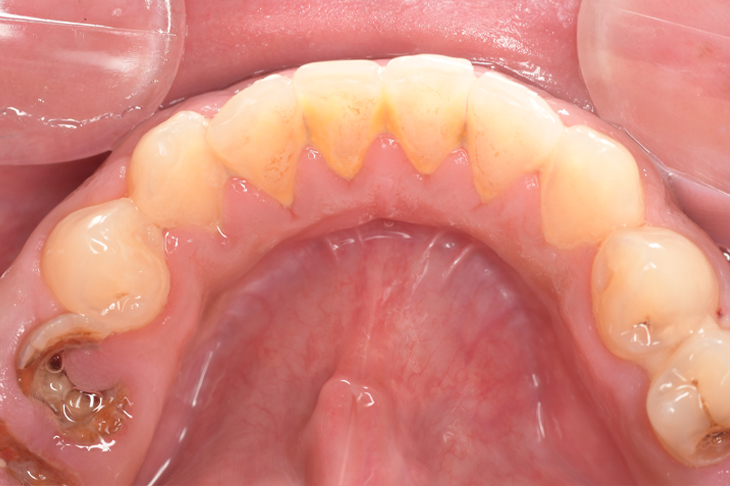

CASE 11

Before

| 年齢・性別 | 32歳・男性 |

| 主訴 | 歯石をとりたい |

| 治療内容 | スケーリング |

| 治療期間 | 30分 |

| 治療費 | 1,500円(保険診療) |

| リスク・副作用 | 知覚過敏、歯肉退縮、出血 |

| 治療方針 | 今後も定期的にクリーニングを行っていきます。 |